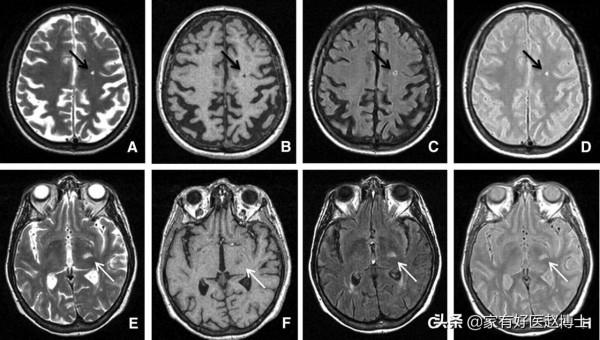

第五個要說的是“腔隙性腦梗塞”,這在顱腦CT或磁共振檢查當中是中老年朋友們比較常見的一種異常結果。

腔隙性腦梗塞不同於大面積腦梗塞,很多時候醫生並不會給與特殊的治療意見。但是,腔隙性腦梗塞被認為與大腦裡小動脈的內皮功能障礙密切相關,因此,也屬於血管老化的一種表現。